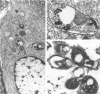

Enterocytozoon bieneusi is a common opportunistic pathogen of human patients with acquired immune deficiency syndrome (AIDS) causing significant morbidity and mortality. In a retrospective analysis utilizing conventional histochemical techniques, in situ hybridization, polymerase chain reaction, and ultrastructural examination, we identified 18 simian-immunodeficiency-virus-infected macaques (16 Macaca mulatta, 1 M. nemestrina, and 1 M. cyclopis) with Enterocytozoon infection of the hepatobiliary system and small intestine. The organisms were readily identified in the bile ducts and gall bladder by special stains and by in situ hybridization using a probe directed against the small subunit ribosomal RNA of human origin E. bieneusi. Infection of the biliary system was associated with a nonsuppurative and proliferative cholecystitis and choledochitis. Hepatic involvement was characterized by bridging portal fibrosis and nodular hepatocellular regeneration accompanied by marked bile ductular and septal duct hyperplasia. Ultrastructurally, all developmental stages of the organism were found in direct contact with the host cell cytoplasm; spores and sporoblasts contained a double layer of polar tubes. Sequencing of a 607-bp segment of the small subunit ribosomal RNA revealed 97 and 100% identity to two clones of small subunit ribosomal RNA derived from E. bieneusi of human origin. Extensive morphological and genetic similarities between the simian and human enterocytozoons suggest that experimentally infected macaques may serve as a useful model of microsporidial infection in AIDS.